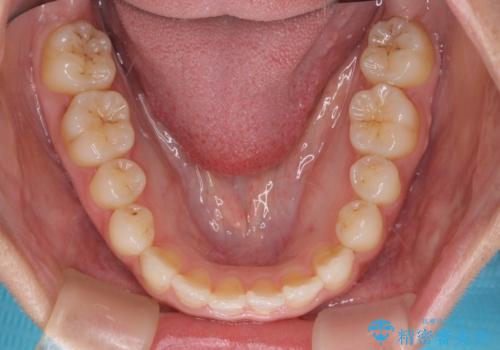

前歯のクロスバイトと変色した歯 ワイヤー矯正とセラミック治療

- 前歯のクロスバイトと神経を取り除いた後に変色してしまった前歯を気にして来院された患者様です。

ワイヤー矯正により矯正治療を行った後に、前歯の補綴治療を行うこととしました。

変色してしまった前歯は、反対側の歯と比べて歯肉が覆い被さっていたため、骨整形を含めた歯周外科処置を行い、歯肉ラインを整えることとしました。

歯周外科処置を行うかどうかは非常に悩んでいらっしゃいましたが、範囲がそれほど広くないため術後の痛みも強くないだろうということで、処置を行うこととなりました。